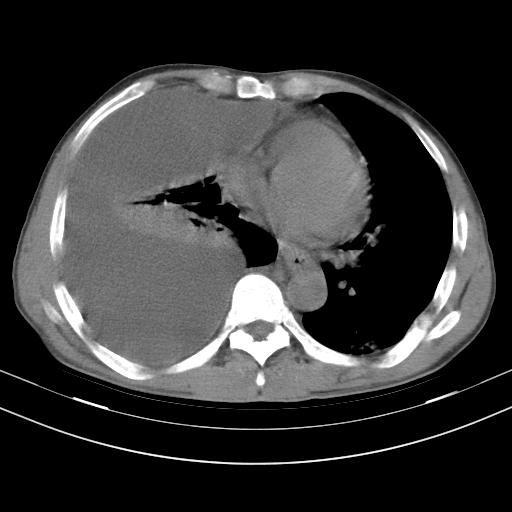

男性,44岁,结核病史多年。现胸闷气短,咳嗽,偶咳血。

1、右侧大量胸腔积液伴右肺压缩性膨胀不全,建议抽液治疗后复查 2、两肺继发性tb伴空洞形成。

1)两肺继发性肺结核伴空洞形成,左肺多发性结核球。2)右侧大量胸腔积液伴右肺部分膨胀不全。3)纵隔淋巴结肿大。

支持1)两肺继发性肺结核伴空洞形成。2)右侧大量胸腔积液伴右肺部分膨胀不全。3)纵隔淋巴结肿大。

吉大一院胸水抽检结果:结核性胸水